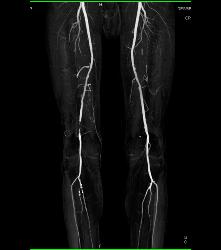

CTA Runoff in 3D With Editing and Peripheral Vascular Disease (PVD)